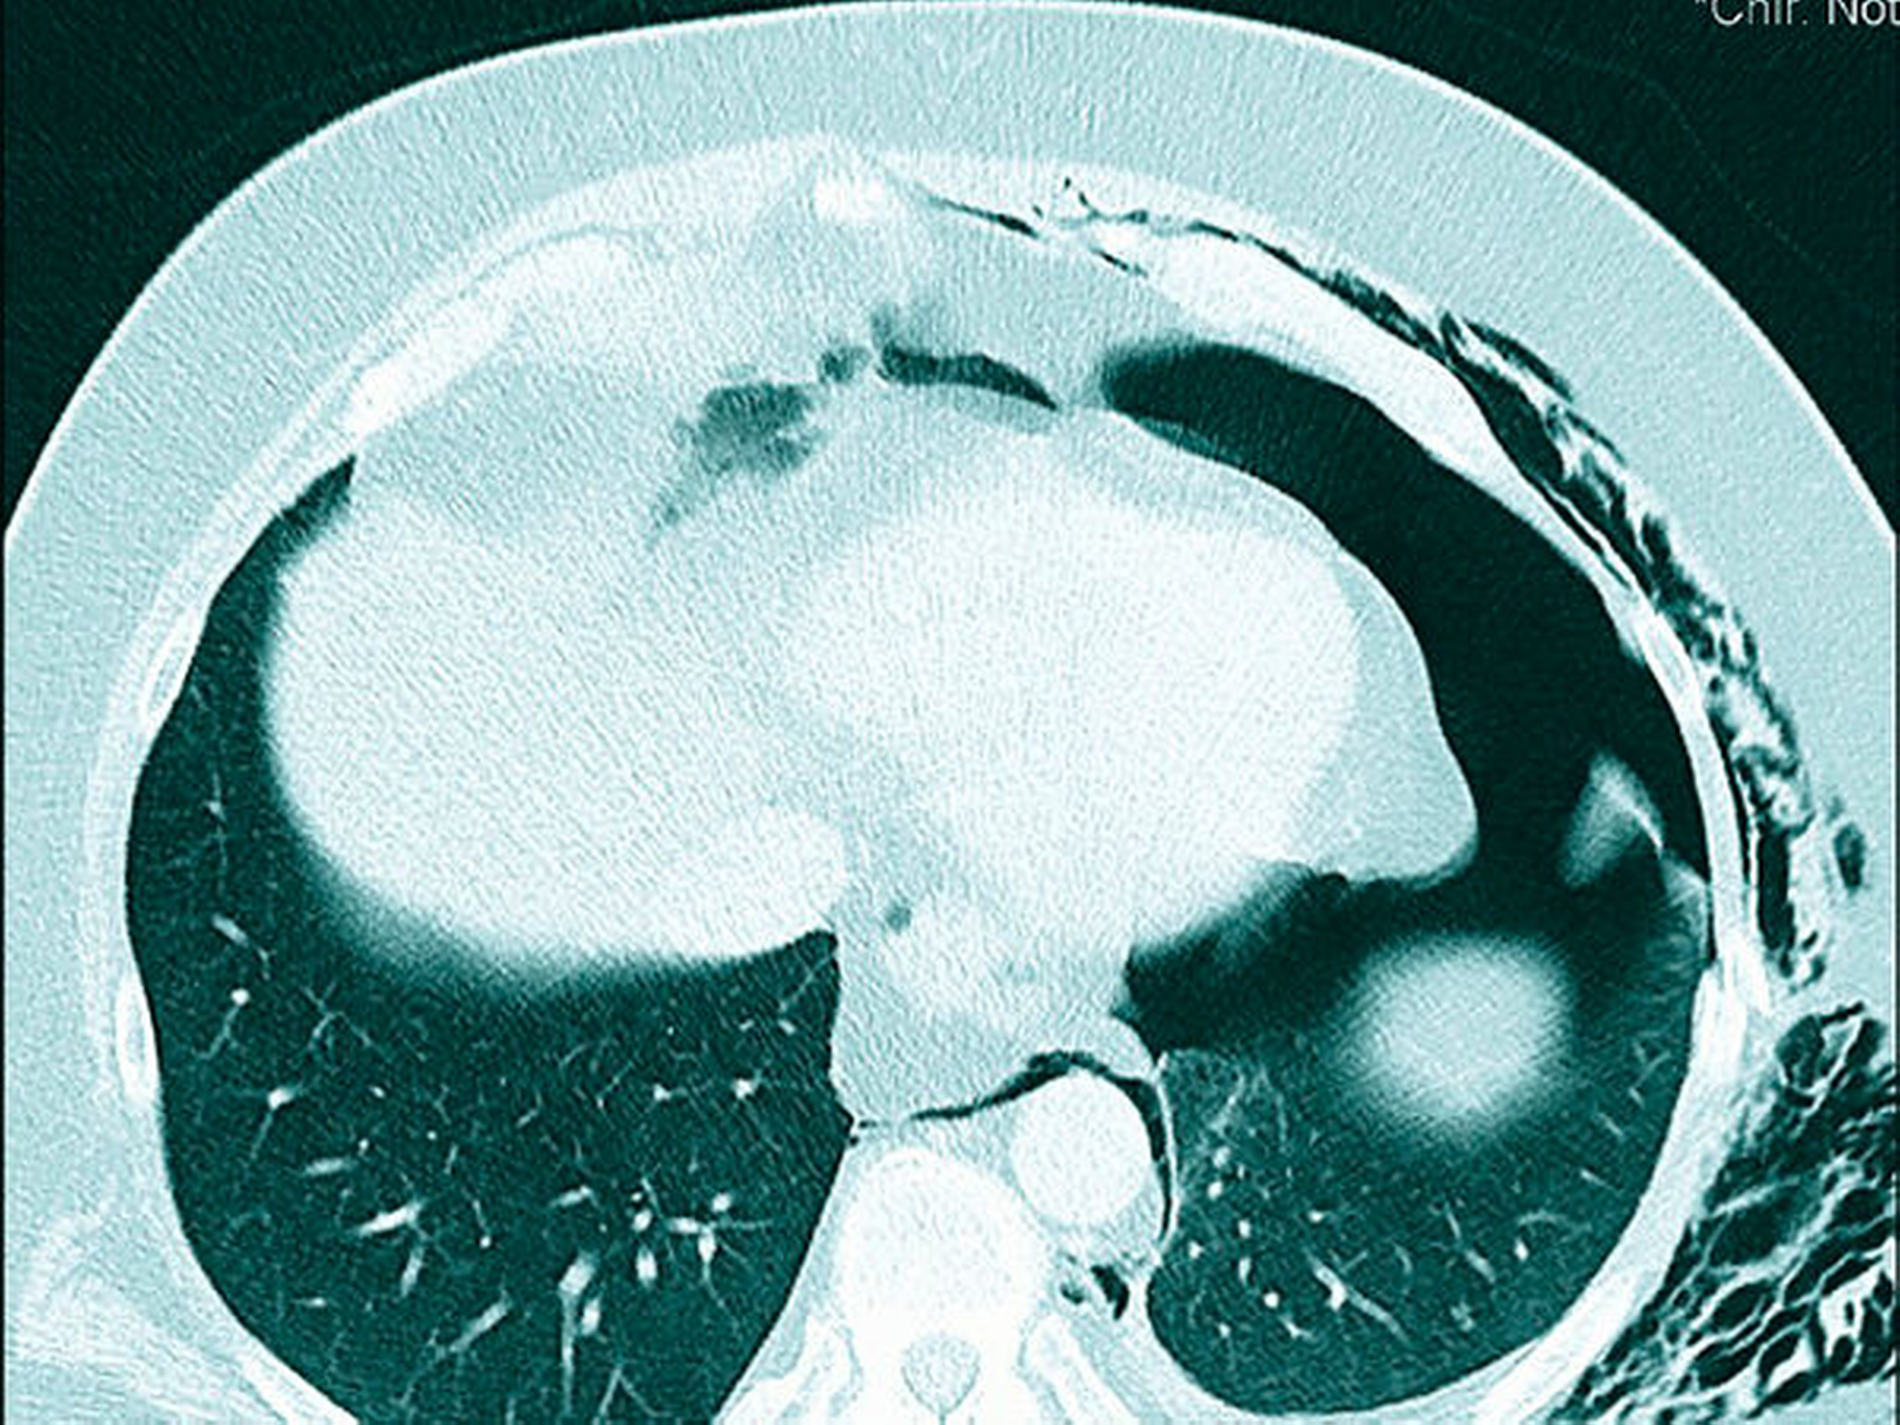

Die daraufhin durch die visceralchirurgische Abteilung durchgeführte Röntgen-Thorax-Aufnahme ergab keinen Frakturbefund im Bereich der Rippen bei ausgedehntem Weichteilemphysem. Bei weiterhin unklarer Diagnose und fehlenden radiologischen Korrelationen wurde auf nachdrückliche Indikation des MKG-Chirurgen eine Computertomografie des Thorax durchgeführt.

Diese zeigte nun Frakturen der siebten bis neunten Rippe links lateral, einen linksseitigen Mantelpneumothorax sowie ein ausgedehntes Weichteilemphysem mit Einstrahlen in den Hals, in den Rücken sowie in das Mediastinum (Abbildung 6).

Nach erneuter Vorstellung des Patienten bei den visceralchirurgischen Kollegen erfolgte nach Anlage einer Bülau-Thorax-Drainage die stationäre Aufnahme.

Im Weiteren zeigte sich ein protrahierter Verlauf mit Hämatothorax und Pleuraempyem. Der Patient verblieb insgesamt dreieinhalb Wochen im stationären Aufenthalt bis zur restitutio ad integrum.